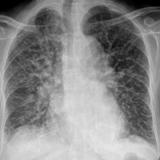

APE 4

Date: 11/05/2005

Views: 2825